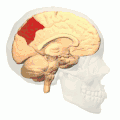

Medial surface of left cerebral hemisphere. (Precuneus visible at top left.) (Anterior to the right.)

In neuroanatomy, the precuneus is the portion of the superior parietal lobule on the medial surface of each brain hemisphere. It is located in front of the cuneus (the upper portion of the occipital lobe). The precuneus is bounded in front by the marginal branch of the cingulate sulcus, at the rear by the parieto-occipital sulcus, and underneath by the subparietal sulcus. It is involved with episodic memory, visuospatial processing, reflections upon self, and aspects of consciousness.